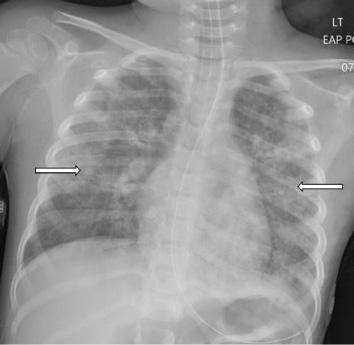

In the ICU she received continued mechanical respiratory support and intermittent diuresis with furosemide to maintain neutral fluid balance. The infiltrates seen on CXR worsened over the next three days with progression of mixed interstitial

and alveolar opacities (Image 3). Despite a worsening CXR appearance, the patient maintained adequate oxygenation with ventilator settings of FiO2 of 30% and positive endexpiratory pressure of 5 mm Hg. She had intermittent fevers and leukocytosis, with a maximum white blood cell count of 26 x 103 cells per microliter (μL) (reference range 4.5 x 103 - 11 x 103 cells/μL); however, antibiotics were deferred. There was no evidence of extrapulmonary organ damage on clinical exam or laboratory testing throughout the duration of her hospitalization. Two respiratory pathogen panels testing for 22 pathogens obtained on hospital days (HD) 2 and 4 were negative, as were blood, urine, and sputum cultures. She was extubated on HD 5. Post-extubation, she required 35-40% FiO2 via heated high-flow nasal cannula at 8-10 L/min for an additional two days as her CXR improved. She required supplemental oxygen until HD 9 and was discharged home the following day.

Chest radiograph on hospital day three showing worsening bilateral infiltrates and progression of mixed interstitial and alveolar opacities